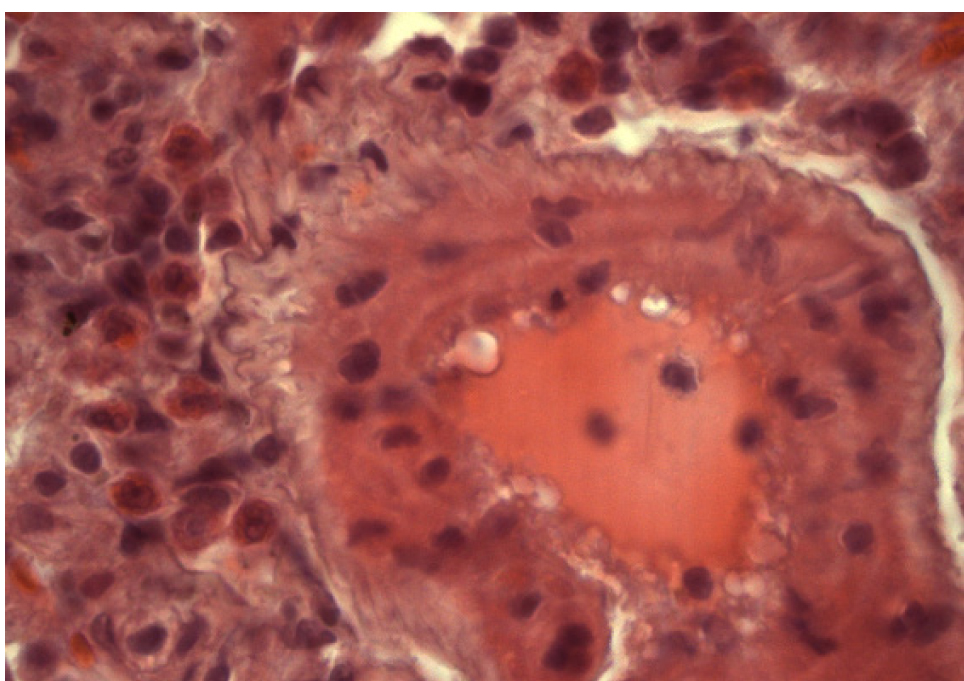

Артерии полнокровны. В их просветах наблюдается гемолиз эритроцитов. В адвентициальной оболочке сосудов выявляются полиморфноцитарные инфильтраты, содержащие эозинофилы (рис. 11), что может служить доказательством развития аллергических реакций.

Рис. 11. Группа 8. Гемолиз эритроцитов в просвете артерии. Периваскулярный инфильтрат, содержащий эозинофилы. Окраска гематоксилином и эозином. Ок. 10. Об. 100. Иммерсия